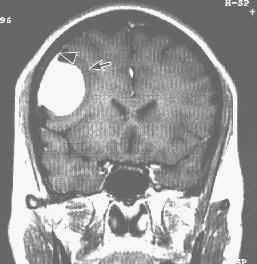

8.影象檢查示眼眶擴大,視神經不規則擴大,視神經管擴大,眶尖部骨質增生或視神經鞘瀰漫鈣化等改變;可對腫瘤定位和定範圍,顯示腫物包繞視神經,或沿蝶骨嵴生長,或向顱內擴展;腫物邊界清楚,密度均勻或不均勻,可被造影劑強化。